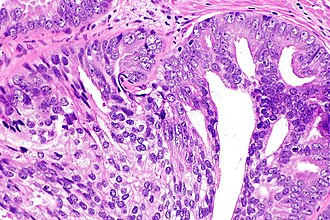

Intraductal carcinoma of prostate. H&E stain. | |

Intraductal carcinoma of the prostate, abbreviated IDC-P, is a proliferation of malignant prostate cells within glands that have an intact basal cell layer.

Required major criteria:[6][7]

- Glands 2x normal (peripheral zone) glands.

- Basal cells present (proven by IHC).

- "Cytologically malignant cells" = nuclear hyperchromasia, nuclear enlargement, nucleoli.

- Fills the lumen ("expansile") but does not have to be "solid".

- Solid = no spaces between the cells.

- Comedonecrosis.

- Branching of ducts at right angles.

- Rounded/smooth gland outlines.

- Two cell populations:

- Malignant population (enlarged nuclei with hyperchromasia and nucleoli) = peripheral location in gland.

- Benign population (smaller nuclei, no nucleoli) = central location in gland.